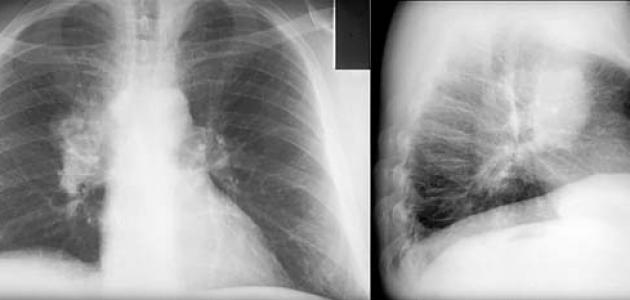

يحدث سرطان الرئة (بالإنجليزية: Lung cancer) عندما تنمو الخلايا غير الطبيعية بشكل خارج عن السيطرة، فلا يقضي عليها الجهاز المناعي ولا تموت تلقائيًا، وبالتالي فإنّ نجاح هذه الخلايا في تفادي الجهاز المناعي سيُشكّل ورمًا في الرئة،[١] وقد تعرف العلماء على العديد من الأسباب التي قد تؤدي لسرطان الرئة، نذكر منها ما يأتي:[٢]